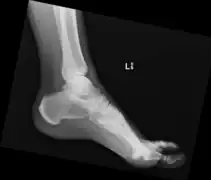

Ectopic calcification and new bone formation in diffuse idiopathic skeletal hyperostosis (DISH)